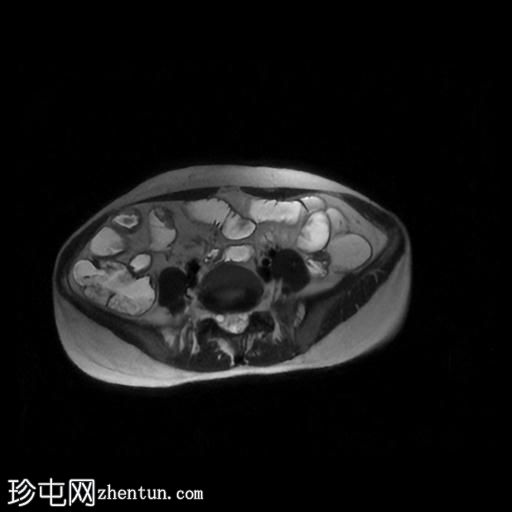

轴位

T2加权像

回肠末端及盆腔回肠肠袢可见长段肠壁增厚及强化,肠周血管丰富,呈“梳状征”,并可见明显的纤维脂肪浸润。

未见瘘管、积液、腹水或梗阻。

磁共振肠道造影(MRE)结果支持克罗恩病的诊断,显示远端及末端回肠以活动

性病

变为主,并可见明显的肠周血管。